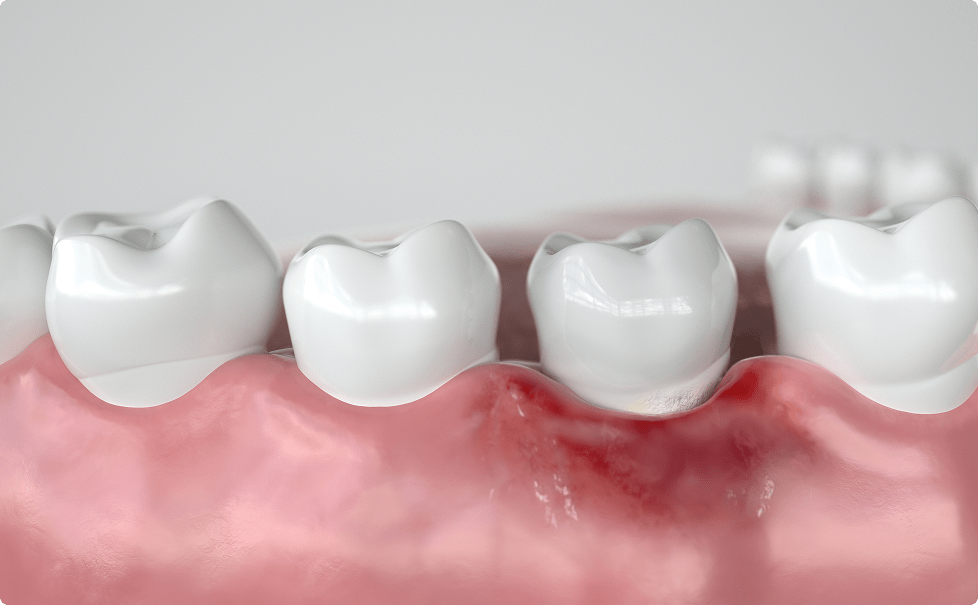

歯肉炎

歯肉炎とは、歯肉溝と言われる歯と歯茎の隙間に磨き残しや汚れが溜まり、細菌が繁殖することで周囲の歯茎が炎症を起こし腫れてしまうことで、ブラッシング時の出血や自然出血が起こる状態を示します。

汚れがこびりついて固まってきますと歯石になります。歯石になってこびりつくと、慢性的に周囲の歯茎が腫れやすくなります。歯肉炎の段階では歯石取りやTBI(歯ブラシ改善)、フロスなどを使用することで改善されます。